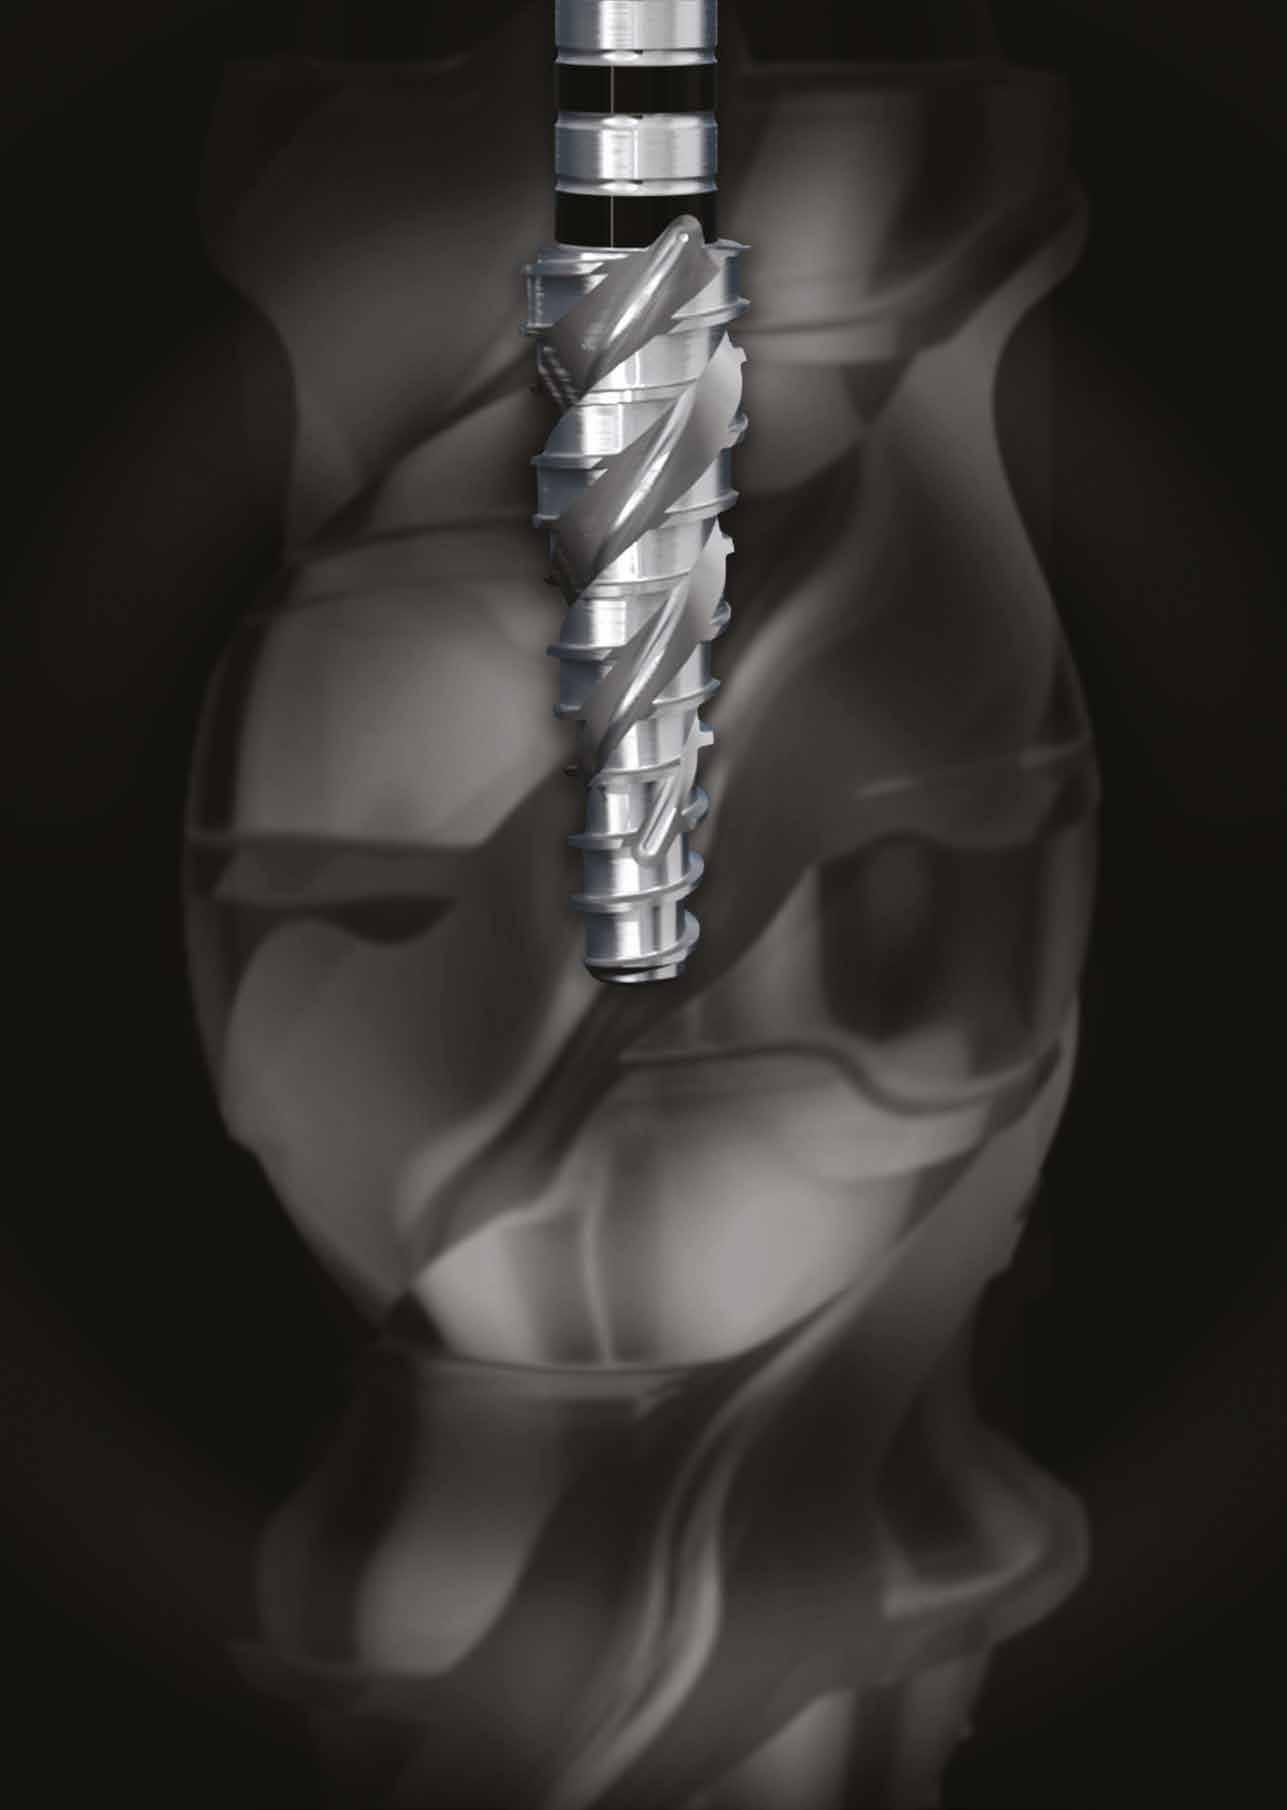

15.30–17.00 Dr. Nuno Pinto (Portugália): A reciproc fájlok fejlődése

Kétségtelenül előrelépés volt a tisztítás és a formázás fejlődésében, az egységes reciproc fájl megjelenése új távlatokat nyitott a fogalmak tekintetében. Feltétlen híve vagyok a reciproknak, mert biztonságosabbnak és egyszerűbbnek tartom, szakértők és kezdők egyaránt használhatják, és lényegében nagy előnyét látom az egyetlen fájlnak és az egyszeri használatnak. E rendszer fejlődése nélkül még mindig kevésbé invazív fájlokat hoznánk létre. Mindannyian tudjuk, hogy egy reciproc fájlnak mindig követnie kell bizonyos követelményeket a minőség és a megbízhatóság fenntartása érdekében, és ez volt a nagy nehézség ennek az új fájlnak a létrehozásában is, azonban sikerült hozzáadni a reciproc fájlok minden megbízhatóságát. A Flatside bevezetése és az alacsonyobb kúp számos előnyt biztosít ennek a fájlnak a versenytársakkal szemben. A Flash a Bondent által kifejlesztett új reciproc fájl, amely előrelépést jelent a tisztítási és formázási eljárás terén.

15.15–16.30 Dr. Cátia Patricio Manilha (Portugália): Gyökércsatornák megmunkálása modern file-rendszerekkel

A gépi tágítás határai, hova fejlődhet a precizitás? Őszintén szólva, jobban szeretem a dugattyús műszerezést, mivel sokkal biztonságosabbnak és bizonyos mértékig könnyebben megoldhatónak tartom az esetek kb. 80%-ában. A VDW elhagyása után meg kellett változtatnom a gondolkodásmódomat, és vissza kellett térnem a forgó reszelőkhöz, de teljesen megváltoztatva annak működési módját, és elkezdtem csak egy reszelőt használni (mintha az egy dugattyús reszelő lenne) az esetek többségében. Egy másik fontos eredmény, hogy ma már a beépített csúcspontkeresővel ellátott motorok szerepe lehetővé teszi a műszereink jobb vezérlését, olyan pontossággal, amely néhány évvel ezelőtt még elképzelhetetlen volt.